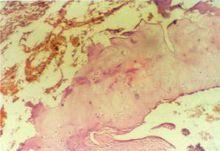

骨細胞

苯乙酸睪酮抑制破骨細胞的骨吸收,還可能刺激成骨細胞形成,尤其是骨膜下皮質骨。苯乙酸睪酮的代謝的產物,尤其是雌激素,可能是雄激素對骨骼作用的主要調節劑。

骨質疏鬆在男子中較為常見,性腺功能低下是男子骨質疏鬆的一個主要危險因素。經促性腺激素激動劑(GnRH-a)治療或者睪丸切除後,骨質密度迅速下降,這可能說明,性腺甾體在維持骨質密度方面有重要的作用。許多關於中老年男子的研究發現,苯乙酸睪酮治療可以降低骨吸收方面的生化指標,而升高皮質骨和骨小梁的骨質密度。